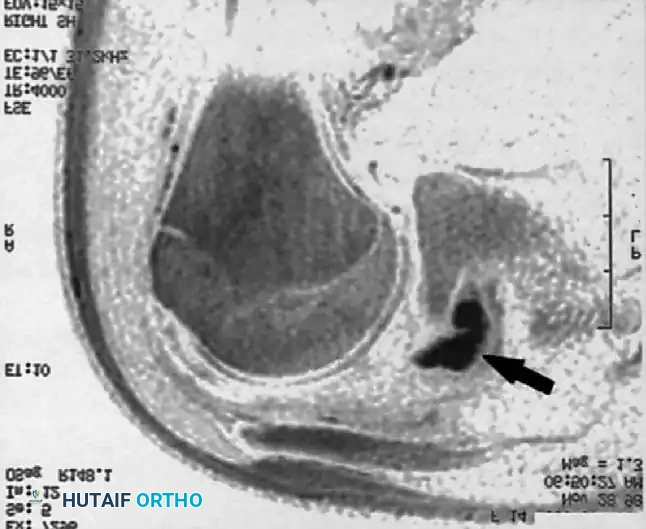

Associated Surgical & Radiographic Imaging